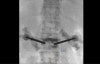

저희 보상파트너는 제3병원 전문의를 통해 후유장해평가를 진행할 수 있었습니다. 요추2번의 압박율을 측정한 결과 27%으로 보험약관 상 뚜렷한 기형30%에 해당하는 수치였죠.